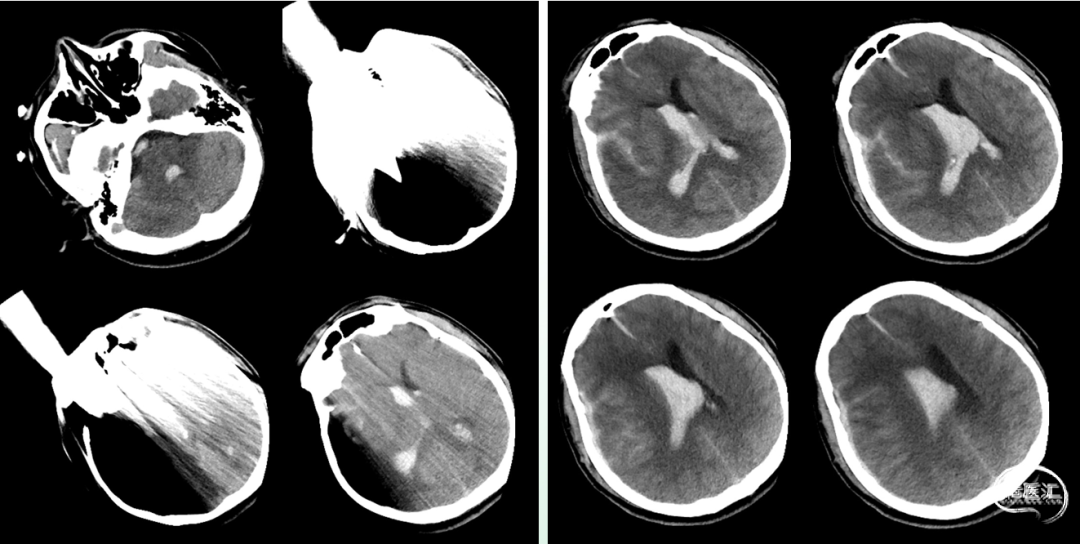

入院时影像

急诊颅脑CT+三维重建:

颅脑锐器损伤并异物存留,异物由右侧眼眶刺入颅内;右侧额颞叶挫裂伤并血肿形成;蛛网膜下腔出血;脑室系统较多积血;右侧额颞顶部少量硬膜下积血。